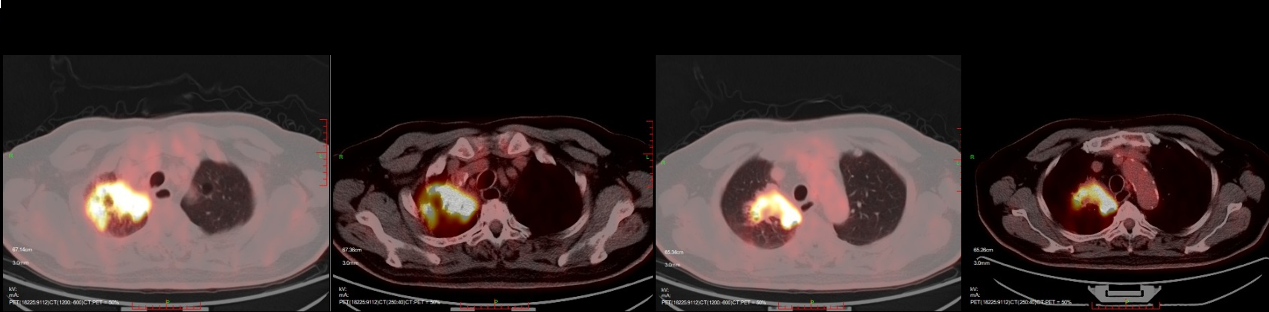

全身PET/CT:声门区病变活检术后,双侧声带前缘壁稍毛糙,糖代谢增高,考虑双侧颈部淋巴结炎性增生。右肺上叶尖后段支气管闭塞,并右肺上叶尖后段团片灶(71mm×48mm),糖代谢增高;综上不除外肿瘤性病变。考虑纵隔、双肺门淋巴结炎性增生。

图4. 入院PET-CT检查